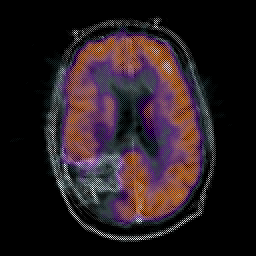

Glioma Overlay -- Slice #13

[Home][Help][Clinical] Slice 13